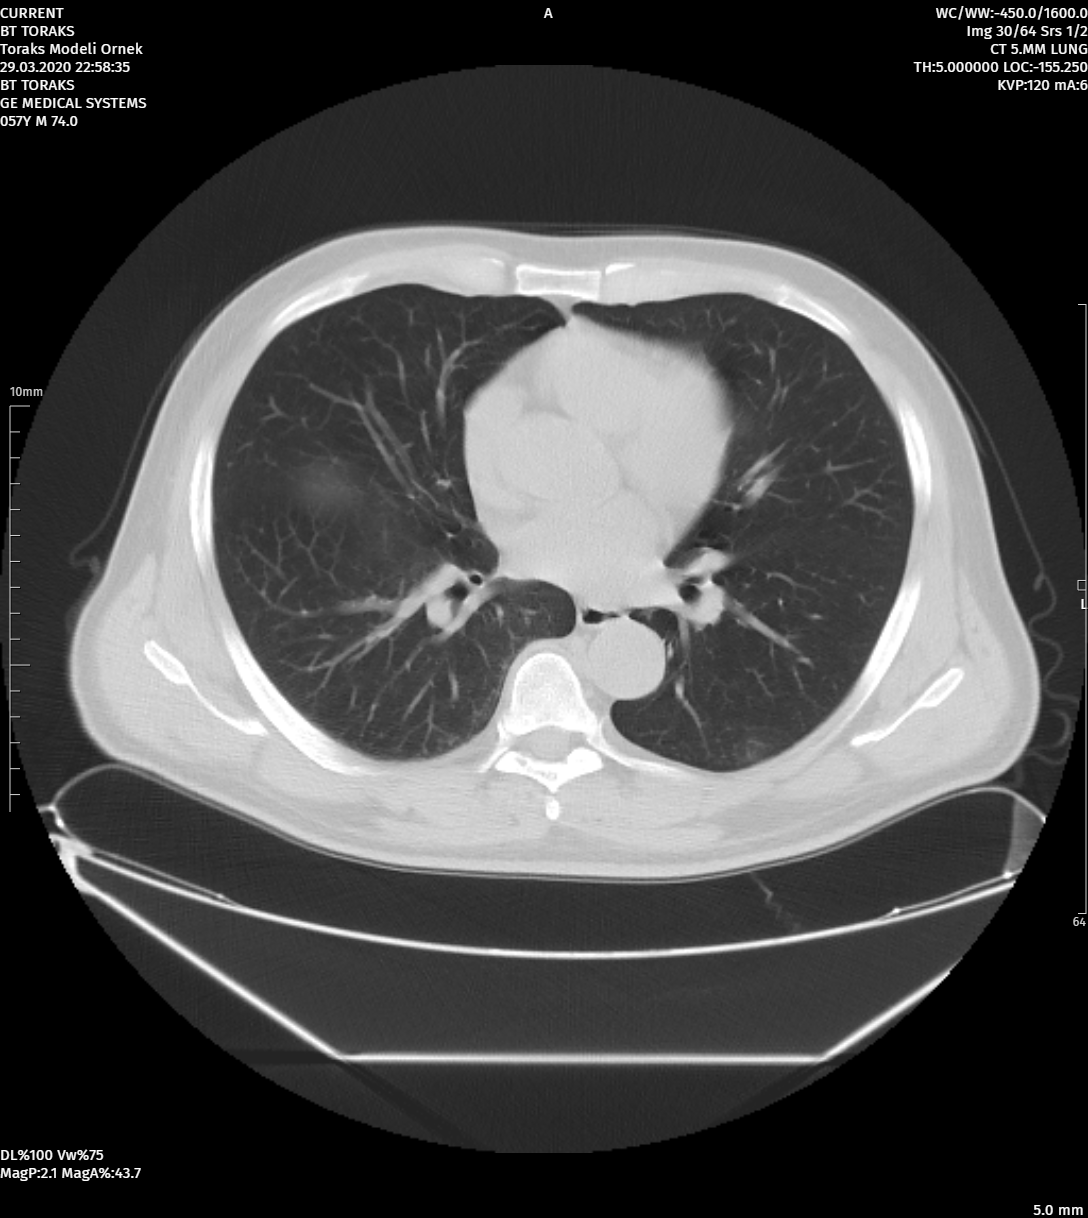

MoreAdvanced Image Processing Tools

Image Processing Tools That Can Work with Different Segmentations